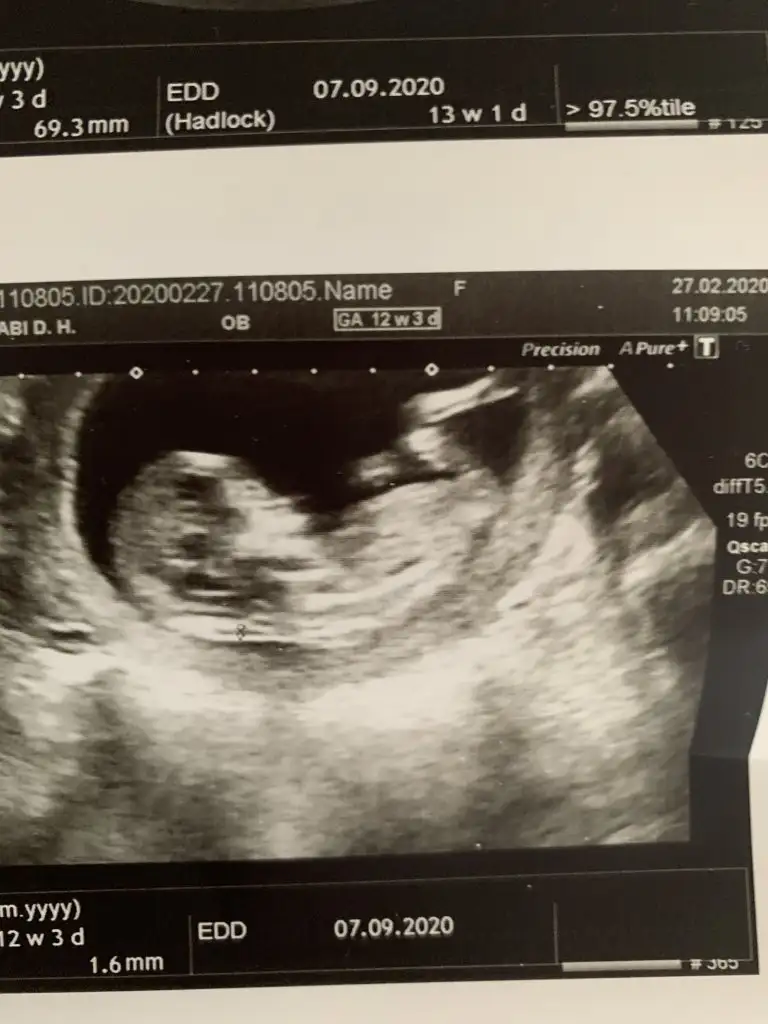

dr soylemeden siz gorun genital nub teorisi ( bebegin cinsiyeti)

iyi akşamlar kızlar bizede bir tahmin Varmı 12+6 haftalığız burada

Senin nubu çizdim cnm arkadaşında çizdim pipide vardı arkadaş pipi olsa söylemezmi deyince bende diğer 10 ve 11 haftasndaki tahminim devam dedim çok istiyordu pipiyi dr görmedi deyince ne kadar geç ögrenise dedim yoksa baya baya pipiydi çizdiğim usg 😊 seninkinide çizdim parelel görünüyor tabi pozisyonu nubu bazen değiştiyor. umarım 31 yanlış tahminim var arasında olmazsın onlar beni yanıtan usgler 😊